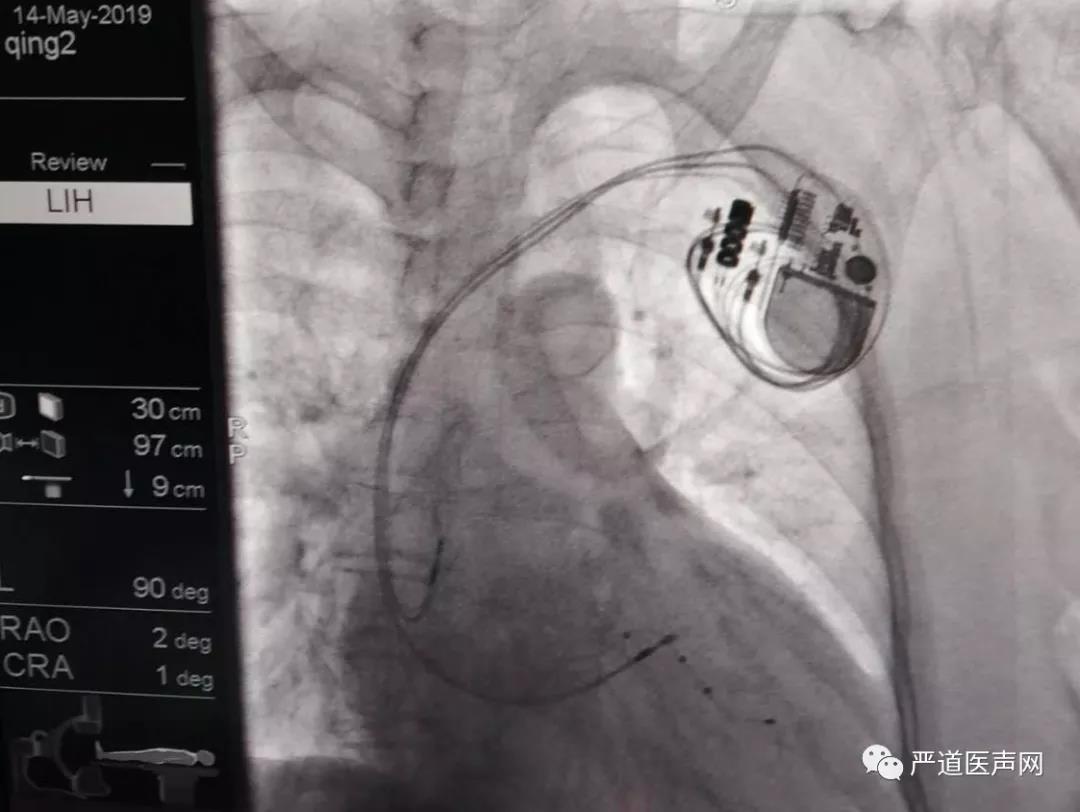

术后正位X光影像

术后左前斜位X光影像